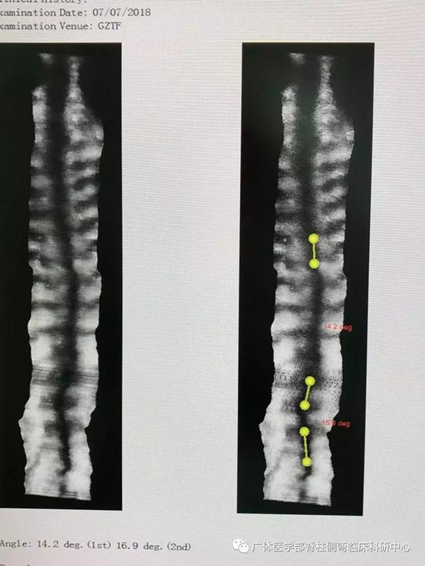

图4所示:自然站姿,三维超声测量度数为24°,与X光片实际测量误差2°

图5所示:指导其进行左腿承重,矫正位站姿,三维超声测量Coob度数为9°

图7所示:自然坐姿,三维超声测量度数T4-T10右凸Scolioscan angle 20°,T10-L4左凸40°(与站立位X光片测量误差2°)

图8所示:右臀承重矫正姿势后,三维超声测量度数T4-T10右凸Scolioscan angle14°,T10-L4左凸17°

图10所示:正常坐位三维超声测量:T1-T4左凸Scolioscan angle 26°,T5-T11右凸24°;T11-L3左凸25°,与站位X光片略有误差均为5°以内。叮嘱该同学特定的坐姿练习:模仿课堂中坐于课室左侧,「右抬头望月」观看幻灯片,保持右臀承重、躯干挺直体位

图11所示:三维超声测量度数(见下图):T1-T4左凸Scolioscan angle 16°,T5-T11右凸14°;T11-L3被矫正未测出度数。合并近胸弯的姿势矫正:改变承重,调整身体力线,保持双肩平衡的姿势体位,具有科学的依据